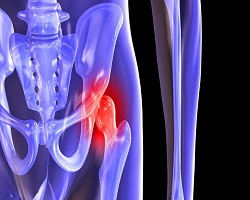

КОКСАРТРОЗА

Коксартроза представља дегенеративну болест зглоба кука која се карактерише пропадањем хрскавице.